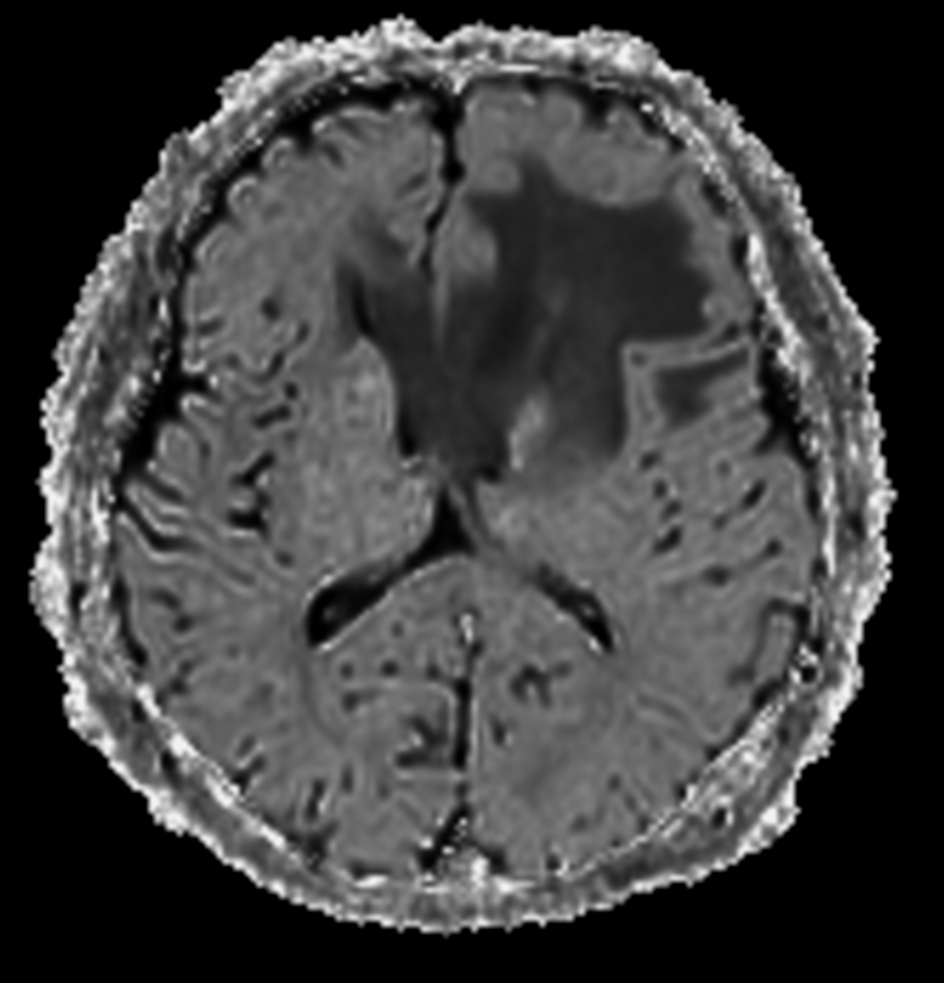

SWIp (minIP)